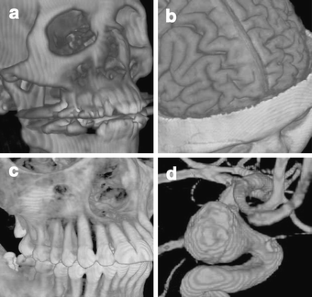

Fig 4.